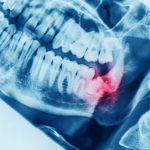

#2 Fogászati és gyulladásos betegségek

A rossz fogak, fogínygyulladás, kezeletlen fogszuvasodás vagy akár a szájpenész is okozhat kellemetlen szájszagot. Ezek a problémák nemcsak a leheletet rontják, hanem komoly egészségügyi kockázatot is jelentenek.

Ezért érdemes félévente fogászati kontrollvizsgálatra járni, hogy időben kiderüljenek a rossz szájszag okai, és el lehessen végezni a szükséges kezeléseket. Szükség lehet például fogtömésre, mikroszkópos gyökérkezelésre vagy akár fogpótlásra is, ha a probléma a szuvas vagy hiányzó fogak miatt alakul ki.